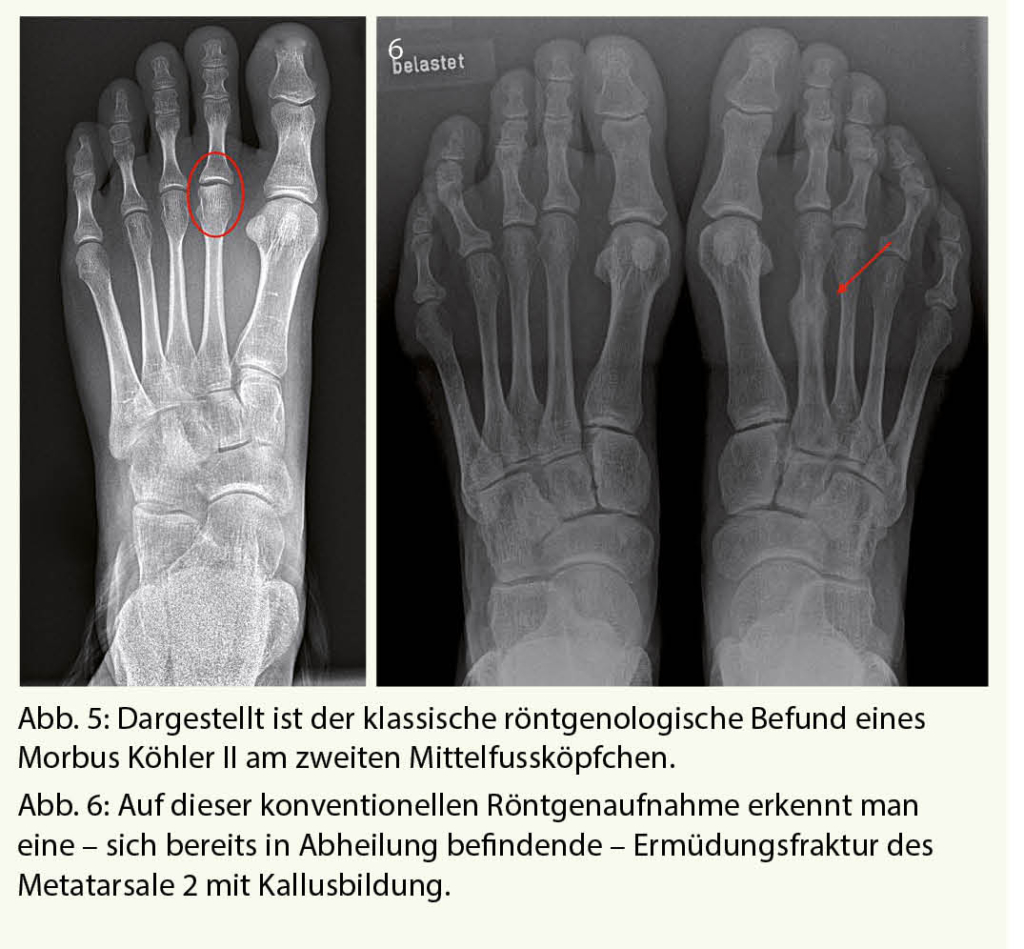

Röntgenaufnahmen unter Belastung gehören zur Standarduntersuchung eines jeden schmerzhaften Vorfusses. Pathologien an den Mittelfussköpfchen oder Ermüdungsfrakturen können hiermit in der Regel zufriedenstellend diagnostiziert werden (Abb. 5 und 6). Dabei muss jedoch beachtet werden, dass Ermüdungsfrakturen oft erst 2-3 Wochen nach Schmerzbeginn anhand der beginnenden Kallusbildung sichtbar werden.

Morbus Köhler II

Der Morbus Köhler II ist eine aseptische Knochennekrose des zweiten, seltener auch dritten Mittelfussköpfchens als Folge einer Durchblutungsstörung unklarer Genese. Primär betroffen sind in der Regel junge Mädchen im Alter von 12 bis 14 Jahren, häufig tritt diese Erkrankung bilateral auf. Wird im akuten Stadium nicht therapiert, kommt es im Verlauf zu einer Verformung des Köpfchens, welche durch die daraus resultierende Inkongruenz zu einer sekundären Arthrose des zweiten bzw. dritten Metatarsophalangeal-Gelenkes führen kann.